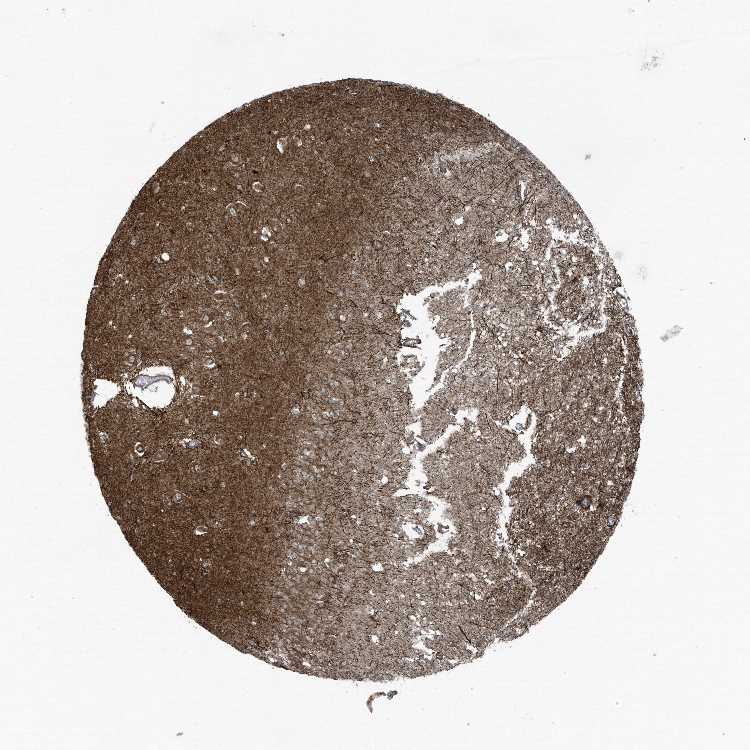

HIPPOCAMPUS - Antibody stainingi

Antibody staining in the annotated cell types in the current human tissue is reported as not detected, low, medium, or high, based on conventional immunohistochemistry profiling in selected tissues. This score is based on the combination of the staining intensity and fraction of stained cells.

Each image is clickable and will lead to virtual microscopy that enables deeper exploration of all samples and also displays staining intensity scores, fraction scores and subcellular localization as well as patient and tissue information for each sample.

Antibody HPA035849Antibody HPA035850

Glial cells MediumNot detected

Neuronal cells MediumMedium